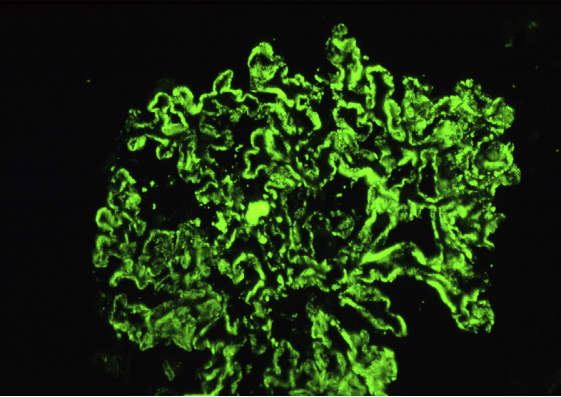

狼疮型肾炎Ⅴ型(膜性LN),弥漫性颗粒状沿着毛细血管环和系膜区染色(免疫荧光,IgG)。

狼疮型肾炎Ⅴ型(膜性LN),弥漫性颗粒状沿着毛细血管环和系膜区染色(免疫荧光,IgG)。